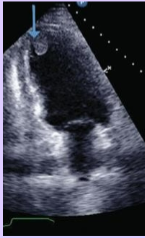

Rhabdomyoma

What is seen in this TTE?

<p>What is seen in this TTE?</p>